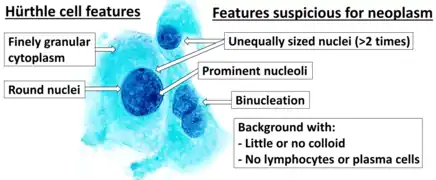

Hürthle cells arise from the follicular epithelium. Key features of these oncocytic cells include a granular cytoplasm that stains eosinophilic (pink on H&E stain) and a vesicular nucleus with a large nucleolus.[6] A Hürthle cell is larger than a follicular cell, and its cellular material stains eosinophilic. Hürthle cells also tend to be large, polygonal cells with distinct cell borders.[4] The cytoplasm of the oncocytes in Hürthle cell adenomas and carcinomas is characterized by an eosinophilic granular nature, which is commonly due to the oncocytes' high content of mitochondria.[6] Some of these cells can contain up to 5,000 mitochondria, which fills the cytoplasm to the point of nearly excluding other organelles.[4] This high amount of mitochondria is reported to be a result of mutations in the mitochondrial DNA.[4] Some scientists have identified these mutations as deletions in the mitochondrial DNA of Hürthle cells found in neoplasms and Hashimoto's thyroiditis.[7]